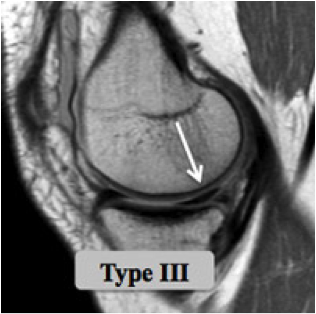

Des examens plus spécifiques comme l'IRM et l'arthroscanner sont demandés si les radiographies sont normales; ils vont permettre de visualiser les structures ménisco-ligamentaires et cartilagineuses de l'articulation.

Les lésions horizontales sont le résultat des forces en glissement. La notion de traumatisme initial peut manquer.

Les lésions intracorporéales sont secondaires aux forces en cisaillement, siégeant souvent dans le segment postérieur du ménisque interne.